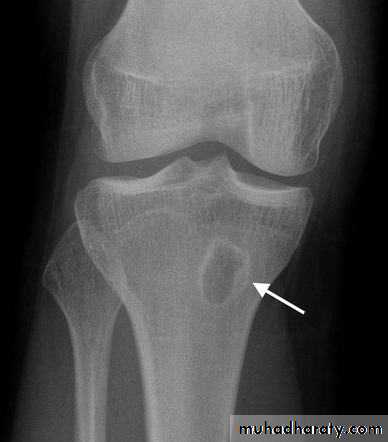

Imaging:

Plain x-ray: the classical appearance is called honeycombed appearance: bone resorption either as a patchy loss of density or as frank excavation around an implant with thickening and sclerosis of the surrounding bone.

CT & MRI: show the extent of bone destruction and hidden abscesses and sequestra.